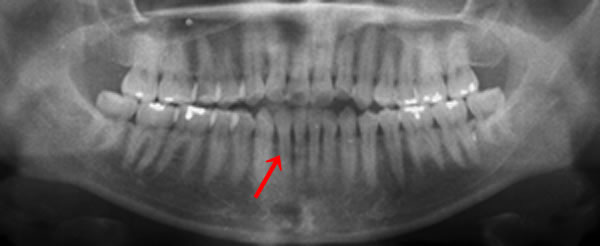

上記写真は30才の方のレントゲン写真です。分かりづらいかもしれませんが、実は歯周病が進行しているため、歯を支える骨が溶けて骨のラインが健康な人よりも下がってきています。

検査をしてみて初めて、ご自身が歯周病であることが発覚したのです。

今まで、他の歯科医院でレントゲンをとっていたにも関わらず指摘されたことが無かったそうです。

今からケアをすれば、将来、歯周病による抜歯を回避できます。